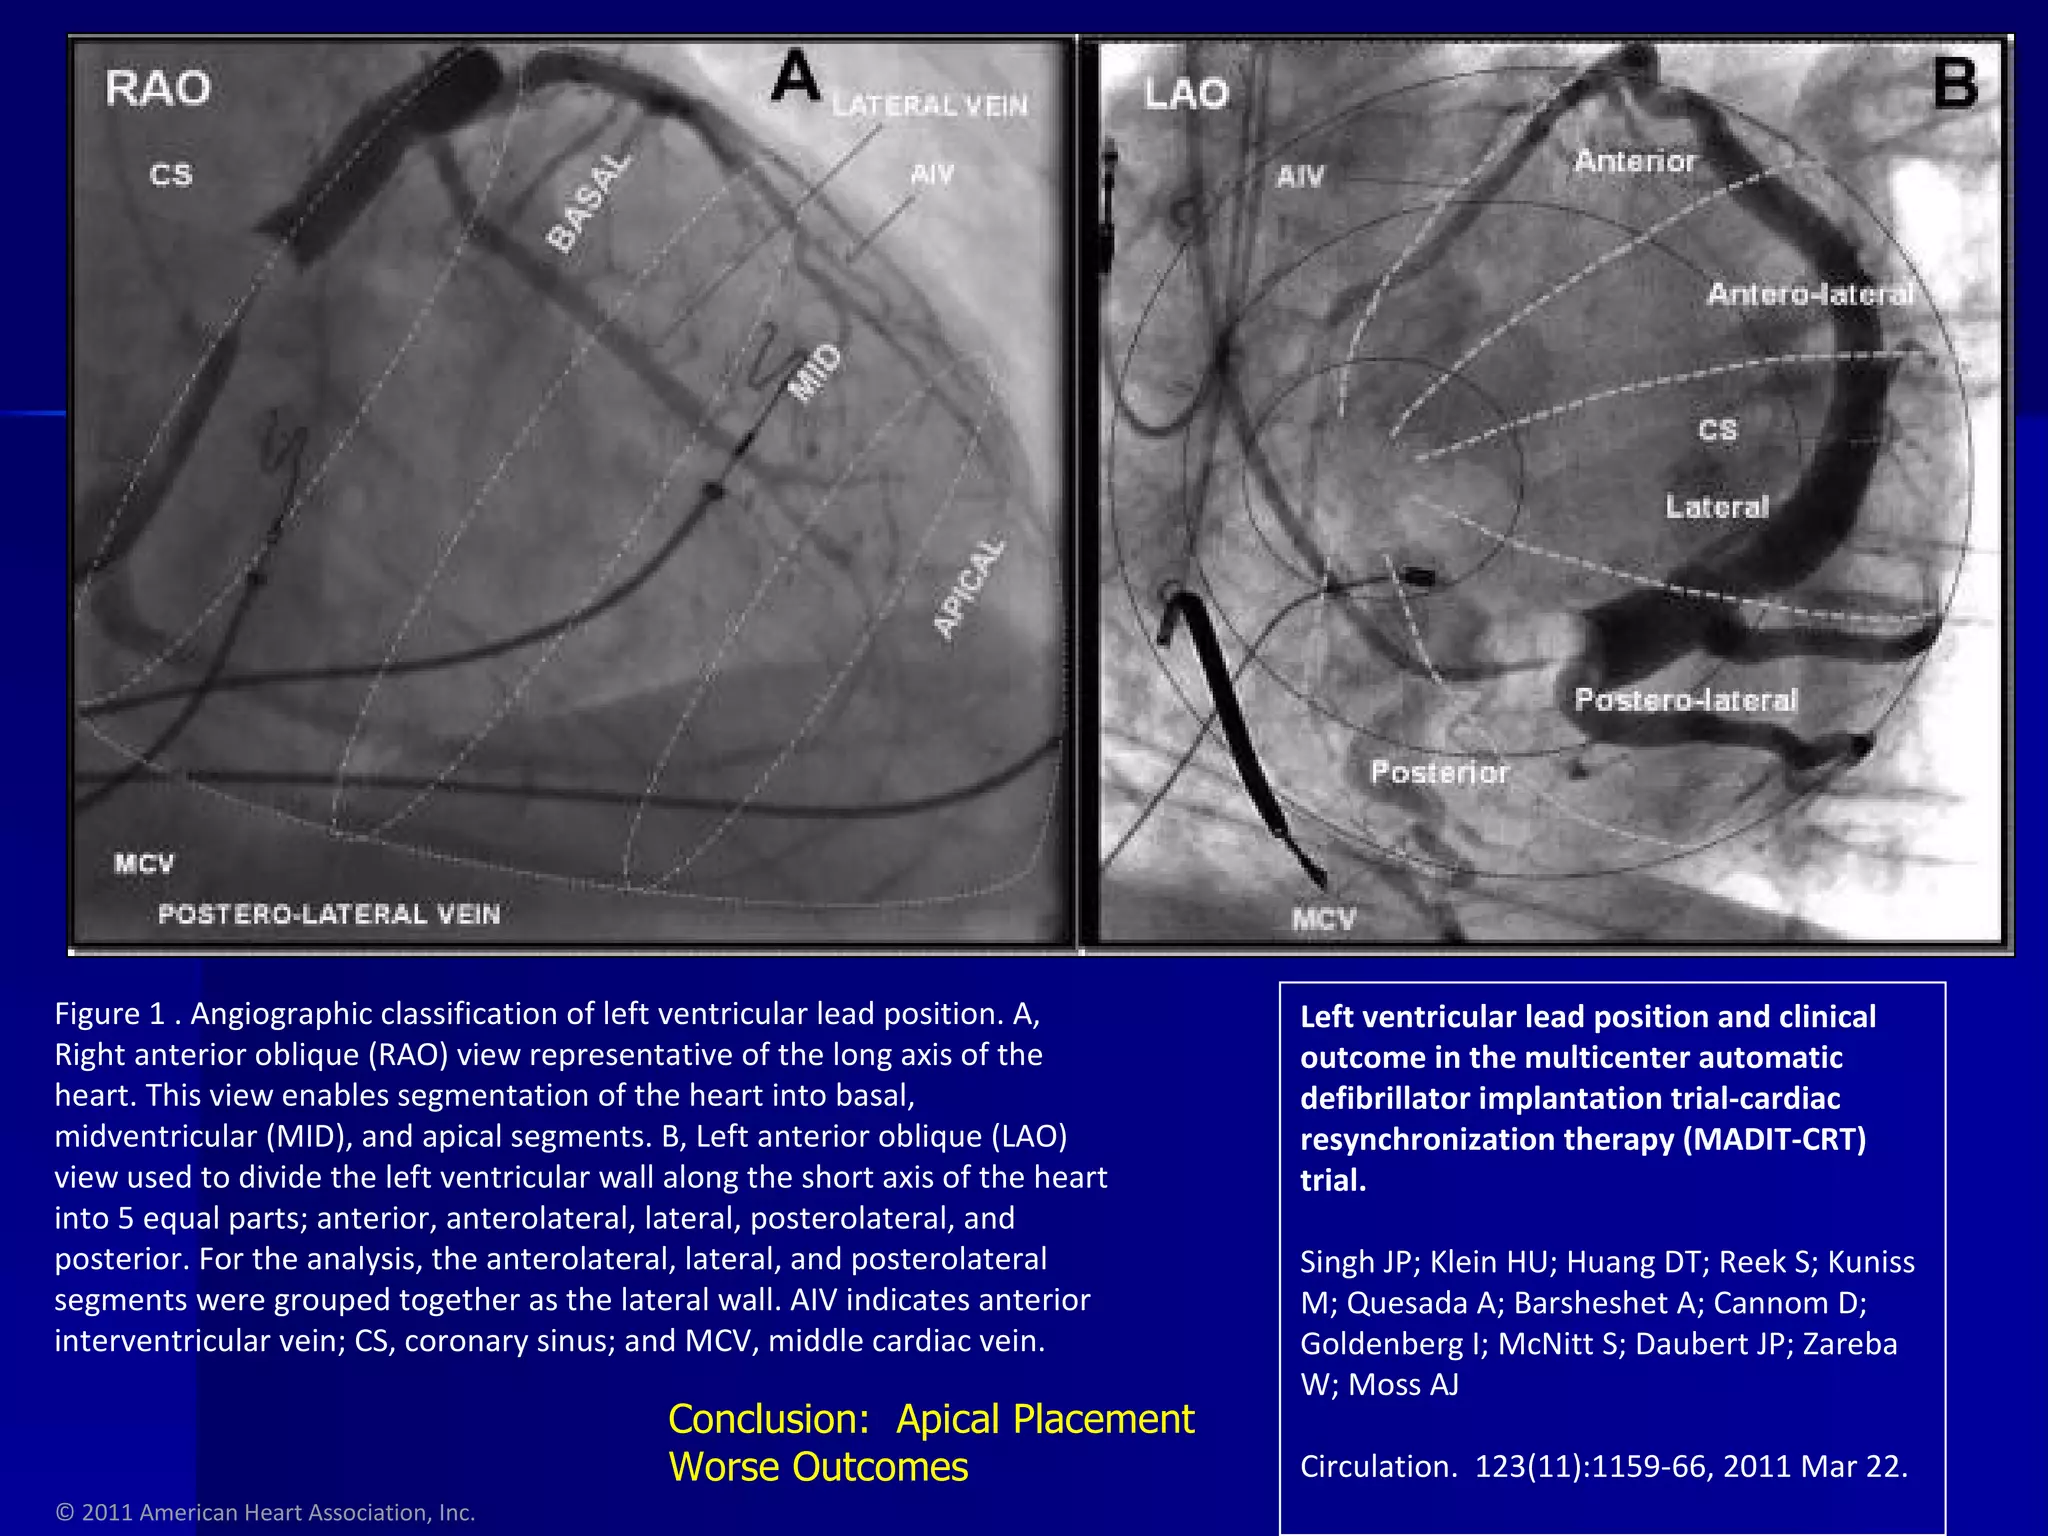

© 2011 American Heart Association, Inc. Left ventricular lead position and clinical outcome in the multicenter automatic defibrillator implantation trial-cardiac resynchronization therapy (MADIT-CRT) trial. Singh JP; Klein HU; Huang DT; Reek S; Kuniss M; Quesada A; Barsheshet A; Cannom D; Goldenberg I; McNitt S; Daubert JP; Zareba W; Moss AJ Circulation.  123(11):1159-66, 2011 Mar 22. Figure 1 . Angiographic classification of left ventricular lead position. A, Right anterior oblique (RAO) view representative of the long axis of the heart. This view enables segmentation of the heart into basal, midventricular (MID), and apical segments. B, Left anterior oblique (LAO) view used to divide the left ventricular wall along the short axis of the heart into 5 equal parts; anterior, anterolateral, lateral, posterolateral, and posterior. For the analysis, the anterolateral, lateral, and posterolateral segments were grouped together as the lateral wall. AIV indicates anterior interventricular vein; CS, coronary sinus; and MCV, middle cardiac vein. Conclusion:  Apical Placement Worse Outcomes

© 2011 AmericanHeart Association, Inc. Left ventricular lead position and clinical outcome in the multicenter automatic defibrillator implantation trial-cardiac resynchronization therapy (MADIT-CRT) trial. Singh JP; Klein HU; Huang DT; Reek S; Kuniss M; Quesada A; Barsheshet A; Cannom D; Goldenberg I; McNitt S; Daubert JP; Zareba W; Moss AJ Circulation. 123(11):1159-66, 2011 Mar 22. Figure 1 . Angiographic classification of left ventricular lead position. A, Right anterior oblique (RAO) view representative of the long axis of the heart. This view enables segmentation of the heart into basal, midventricular (MID), and apical segments. B, Left anterior oblique (LAO) view used to divide the left ventricular wall along the short axis of the heart into 5 equal parts; anterior, anterolateral, lateral, posterolateral, and posterior. For the analysis, the anterolateral, lateral, and posterolateral segments were grouped together as the lateral wall. AIV indicates anterior interventricular vein; CS, coronary sinus; and MCV, middle cardiac vein. Conclusion: Apical Placement Worse Outcomes